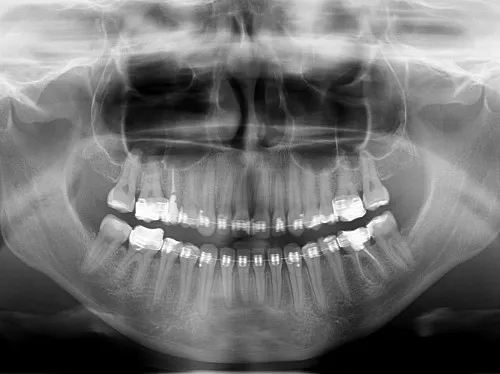

Kiedy mówimy o diagnostyce stomatologicznej, zwłaszcza tej wykorzystującej promieniowanie rentgenowskie, zasady są dość jasne. Na badania diagnostyczne, takie jak rentgen zębów (zdjęcie punktowe pojedynczego zęba, zdjęcie pantomograficzne, czyli panoramiczne szczęki i żuchwy), zawsze potrzebne jest skierowanie od lekarza dentysty. Ta zasada obowiązuje niezależnie od tego, czy badanie jest wykonywane w ramach NFZ, czy prywatnie. Skierowanie jest niezbędne, ponieważ lekarz dentysta musi ocenić zasadność wykonania badania i określić jego zakres, minimalizując tym samym ekspozycję pacjenta na promieniowanie.

Podobnie, jeśli potrzebna jest bardziej zaawansowana diagnostyka, taka jak tomografia komputerowa stożkowa (CBCT) szczęki i żuchwy, również wymagane jest skierowanie od lekarza dentysty. CBCT to badanie 3D, które dostarcza niezwykle szczegółowych informacji o strukturach kostnych i zębach, co jest kluczowe np. przed zabiegami implantologicznymi, skomplikowanymi ekstrakcjami czy w diagnostyce zmian patologicznych. Także w tym przypadku, bez względu na to, czy badanie jest refundowane, czy pełnopłatne, skierowanie jest obowiązkowe.